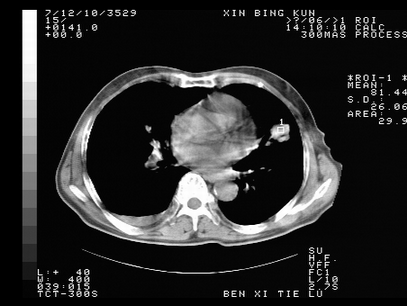

标题: CT10820:男,73岁,病史肺TB,现病史肺炎,直肠CA术后 [打印本页]

标题: CT10820:男,73岁,病史肺TB,现病史肺炎,直肠CA术后

双肺间质改变,依据病史双肺多发结节灶考虑转移,少量胸水.

1.两肺结核.2.两肺多发转移瘤.3右侧少量胸腔积液4.主动脉钙化.

双肺多发结节及条片状致密影,右侧少量胸腔积液。临床:直肠ca术后,肺tb病史。综合考虑:1 双肺转移!2 继发性肺结核合并感染!

此人病史较复杂,原有肺结核,直肠癌术后。肺部病灶形态亦呈多形性。因此,不可仅以一种病来解释肺部的病变。双肺多发的类圆形结节灶,结合病史还是首先考虑转移瘤,而双肺其余病灶还需结合化验室检查,结核或肺部感染在无其它检查资料的情况下不好排除。还是那句话----放射科医生不是开照像馆的,我们也是医生,看片一定要多结合临床及其它检查资料。要当一名合格的放射科医生,并不比当一名临床医生容易,我们可别把自已不当医生看。

两肺多发结节影,并见滋养动脉与其相连,考虑 两肺转移. 右侧胸腔积液考虑胸膜转移.

左肺上叶下叶背段,右肺中下叶见多发斑片状、条索状高密度影,兵变周围小结节影形成“树芽”样改变。 左肺上叶舌段近前胸壁处及右肺中叶内侧段见结节影。右侧胸膜腔内见液体密度区。纵隔内未见明确增大淋巴结。考虑左肺上叶舌段近前胸壁处及右肺中叶转移瘤可能性大。两肺继发型肺结核。右侧胸腔积液。

还有心包少量积液。